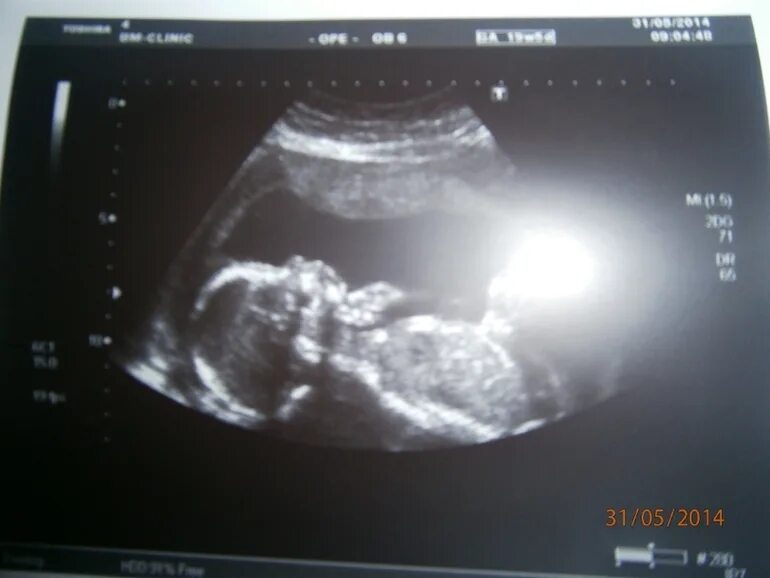

Узи 17 недель девочка